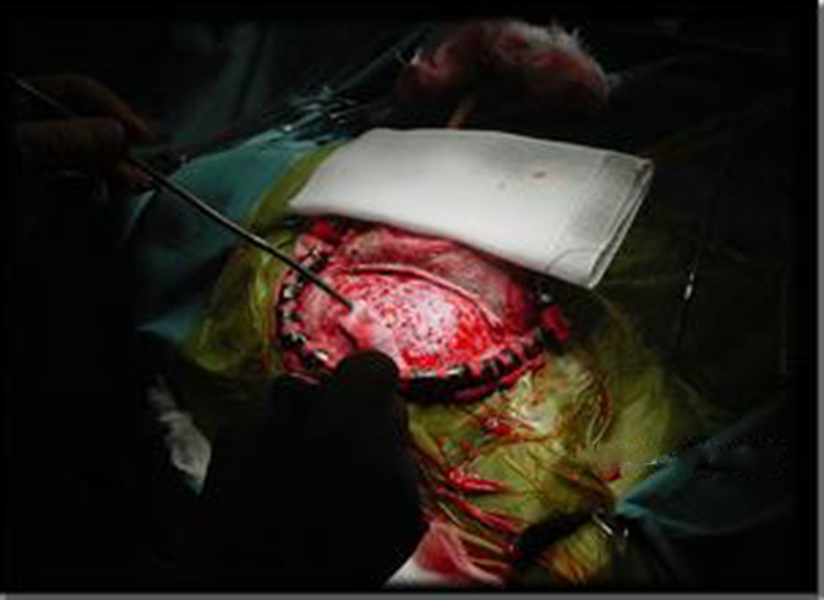

幼兒煙霧病腦手術

幼兒頭部手術煙霧病

煙霧病幼兒頭部

A:煙霧病目前有兩種手術方式,分別是血管搭橋手術和血管貼敷手術。血管搭橋手術是將顳淺動脈進行剝離,然後與大腦中動脈進行吻合搭橋。而血管貼敷手術是將顳淺動脈剝離後貼敷到腦的表面上。通過這兩種手術方式,主要的起到的作用是建立新的側枝循環,從而供應腦……

A:煙霧病的主要手術方式是進行顳淺動脈搭橋手術或者貼敷手術,這種手術是需要進行全身麻醉的,因此做完手術後需要臥床,並且密切觀察病情變化。如果術後恢復順利,那手術後兩三天就可以開始下床活動,早下地能夠起到改善下肢循環的作用,能夠預防出現下肢的深靜……